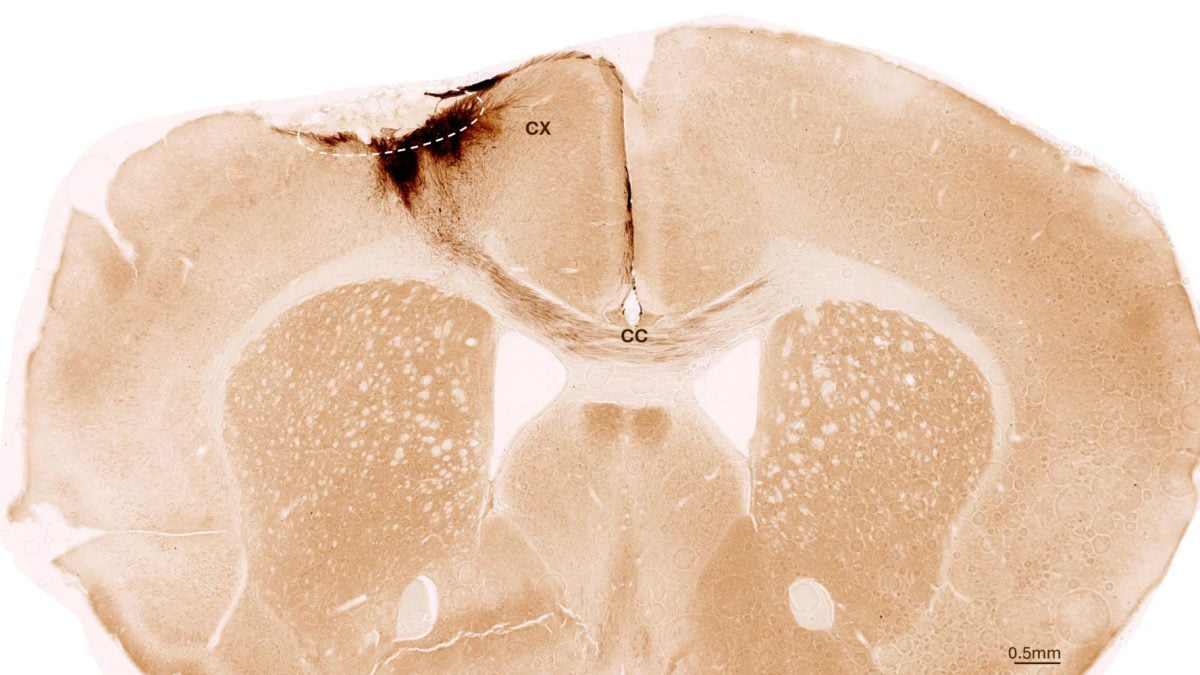

Et nytt forskningsgjennombrudd fra Universitetet i Zürich gir håp til millioner av pasienter som rammes av hjerneslag hvert år. Ved hjelp av stamceller har forskere klart å reversere skadene etter slag hos mus, gjenoppbygge hjerneceller og til og med gjenopprette bevegelighet.

I studien transplanterte forskerne menneskelige stamceller inn i den skadede delen av musenes hjerner. Resultatene var oppsiktsvekkende: Stamcellene overlevde, utviklet seg til nye nerveceller og kommuniserte med de eksisterende hjernecellene.

Forskerne observerte også andre tegn på heling: nye blodårer ble dannet, betennelsesreaksjoner ble dempet, og blod-hjerne-barrieren ble styrket. Til og med musenes motoriske evner ble bedre – bekreftet gjennom AI-analyse av ganglaget.